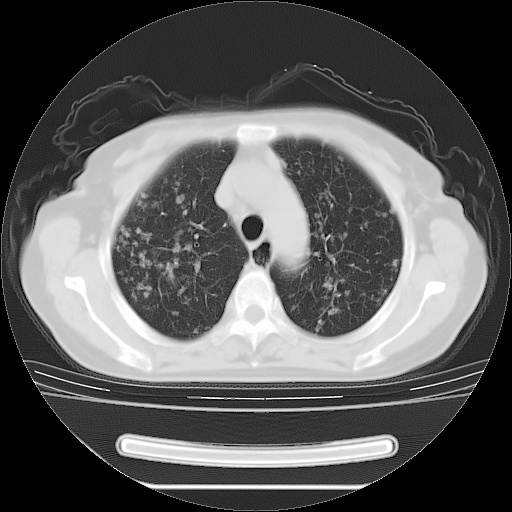

ct示两肺粟粒状病灶,以两肺上叶尖后段及下叶背段分布为主;首先考虑结核。请战友们分析。

考虑 1 弥漫性泛细支气管炎, 2 结核不除外/.  有小叶中心结节 和 树芽征!!

两肺内病灶呈小结节状和树芽状,纵膈的肿大的淋巴结密度不均匀,并见有钙化,考虑为两肺结核可能更大些。

两肺内病灶呈小结节状和树芽状,纵膈的肿大的淋巴结密度不均匀,并见有钙化,多形态病灶,考虑为两肺结核,肝内考虑小囊肿。

病灶以结节为主,大部分边界清楚,分布不均,病灶形态较单一,偶见空泡征,纵膈淋巴结肿大钙化,无结核中毒症状考虑 感染性病变【真菌类可能性大】,细支气管肺泡癌。其他待排